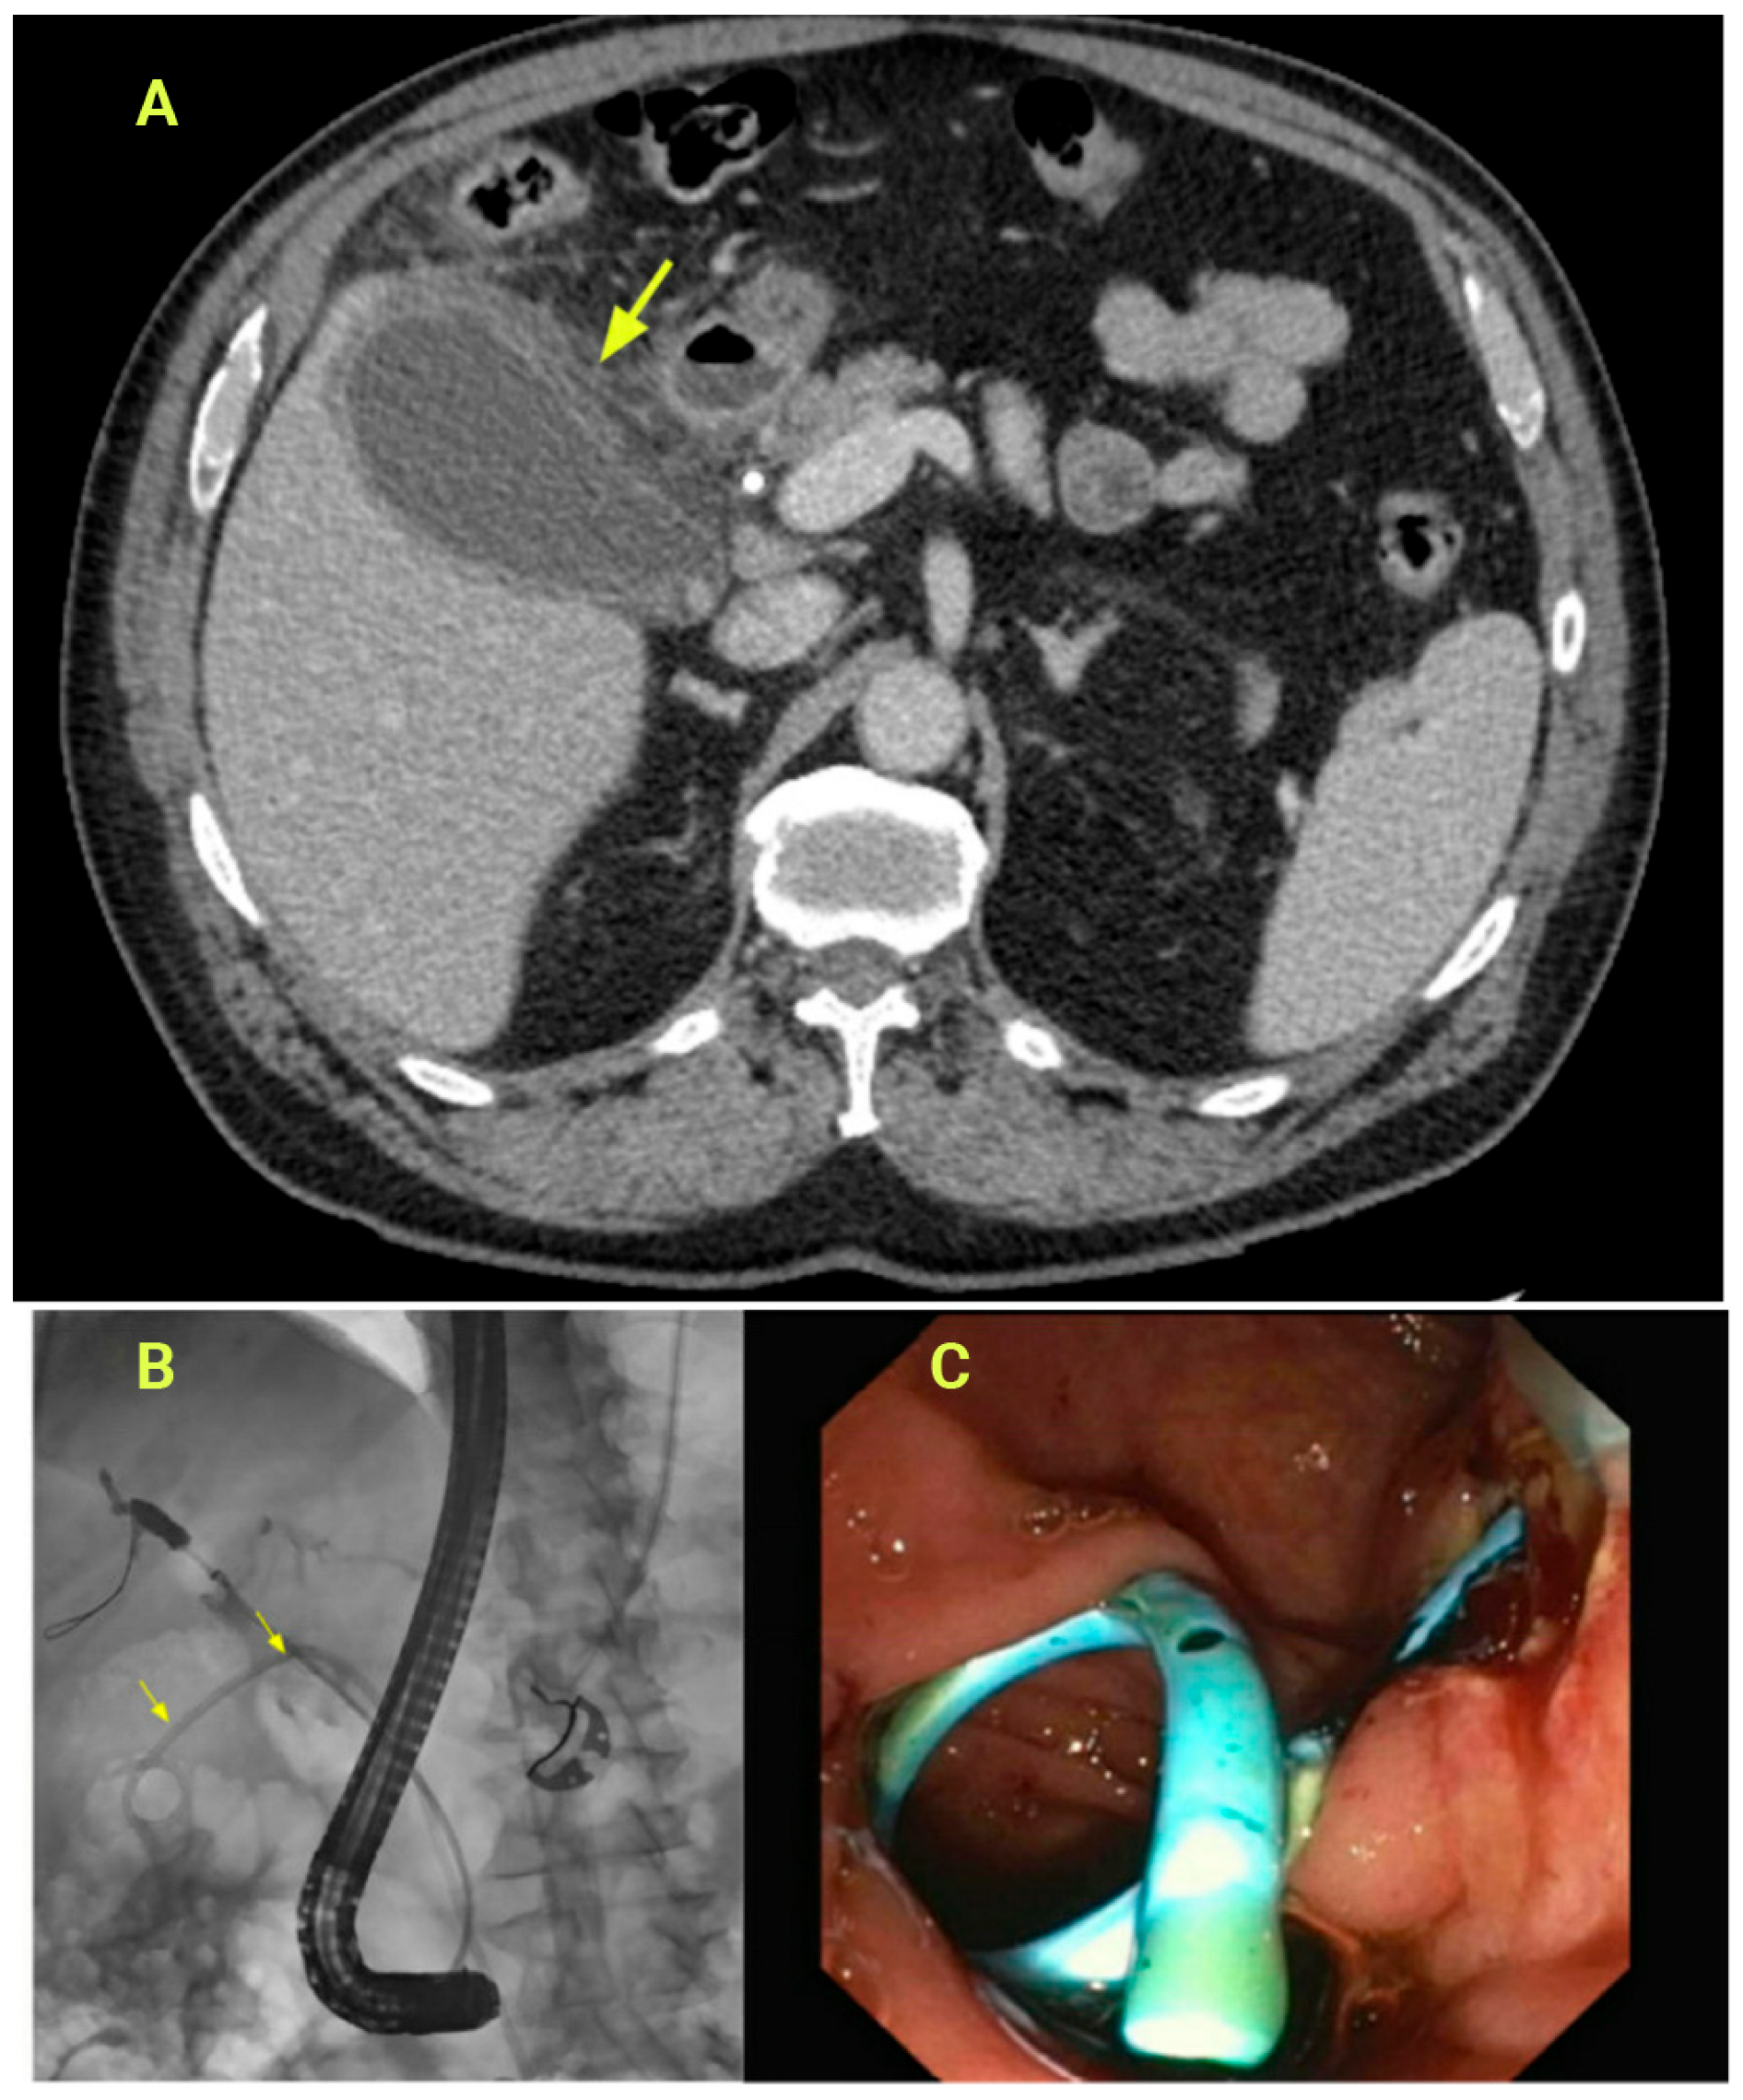

3.3. Transpapillary Gallbladder Drainage (ETP-GBD)

3.4. Endoscopic Ultrasound-Guided Gallbladder Drainage (EUS-GBD)